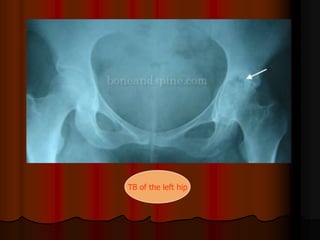

Imaging: early; bone rarefaction with preserved joint space.

later; articular cartilage erosion leading to permanent

joint destruction.

TB of the left hip